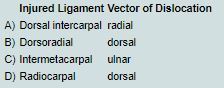

When considering dislocations of the thumb carpometacarpal (CMC) joint, which of the following is most correct regarding which vector of dislocation would occur with injury to the stabilizing ligament?

The correct response is Option B.

The CMCJ is very important for hand function and plays a key role in pinch and grasp. The increased range of motion inherent to the thumb CMCJ is attributed to the anatomy of the joint. The biconcave saddle shaped articular surface of the CMCJ also provides some inherent stability. Motion allowed by the joint includes flexion, extension, adduction, abduction, circumduction. Stabilizing ligaments and joint capsule further reinforce the joint, thus thumb CMCJ dislocations are rare injuries. These injuries account for less than 1% of hand injuries.

There are five major stabilizing ligaments to the CMCJ: anterior (volar) oblique, ulnar collateral, intermetacarpal, dorsoradial, and dorsal (posterior) oblique. These ligaments are critical stabilizers during motion. The volar oblique ligament and dorsoradial ligaments are considered to be the most important resistive forces in dislocation in cadaver studies. Reports of traumatic thumb CMCJ dislocation have been in a dorsal vector. The volar oblique ligament was originally thought to be the critical resistive ligament; however, recent literature has supported the dorsal complex (includes the dorsoradial and posterior oblique ligaments) are the most critical for restraint of the joint, thus are injured in dorsal dislocations. Timely recognition is important for these injuries as immediate reduction and casting or splinting for 4 to 6 weeks may be adequate to prevent recurrence. However, these injuries are often missed on radiologic examination or may be persistently unstable. Closed reduction and Kirschner wire fixation may be adequate for treatment in persistently unstable injuries. Some authors advocate for open reduction and ligament reconstruction. Delayed treatment especially beyond three weeks will likely require open reduction and ligament reconstruction. These injuries are often missed on x-ray examination as they can be subtle especially in the setting of more obvious trauma. Inadequate treatment puts these patients at increased risk for subsequent posttraumatic osteoarthritis given the joint malalignment.

The radiocarpal and dorsal intercarpal ligaments are wrist stabilizer not thumb CMCJ stabilizers.